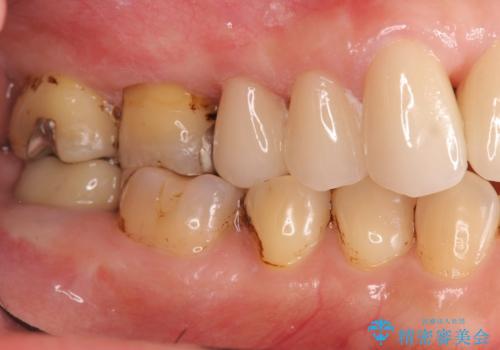

歯周病に対する全体治療

治療期間はかかりましたが、しっかりと歯周病治療・インプラント治療を行ったおかげで歯周病の状態は非常に良くなり、安定した咬合関係を確立することができました。

再生治療、歯周外科を行うことで歯周病治療を行い、残すことのできる歯の歯周環境を整える。

残すことのできない歯は抜去したのち骨造成を含めたインプラント治療を行い、しっかりとした咬合関係を確立していきます。